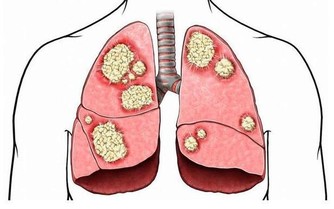

消化道出血或惡性腫瘤:消化道出血時,血液在患者的腸道中聚集。胃酸及腸道細菌將血液分解後,排出的屁有腥臭味。患腸道惡性腫瘤時,癌組織糜爛、出血,再加上細菌的分解發酵作用,也會使放出的屁有腥臭味。

腸道細菌感染:腸道內的細菌毒素通常可使腸黏膜遭到破壞,黏膜上皮細胞壞死並脫落,經過發酵之後,這些物質可產生惡臭氣體,並隨屁一起排出。

若屁奇臭難聞,可能有消化道出血、菌痢、阿米巴痢疾、潰瘍性結腸炎、出血性小腸炎等炎症。此外,惡性腫瘤晚期,因癌腫組織糜爛,蛋白質腐敗,由於細菌的作用,放出的屁也會很臭。愛放屁且經常放臭屁的人就有可能患上大腸疾病,這時你就需要前去診斷了。

放屁是一種正常的生理反應, 人人都要放屁。一個身體健康的人每天都會放幾個屁。屁在體內運動時會促進腸道蠕動, 排出體外時會帶走許多有毒、有害的氣體, 對我們健康非常有益。天天有屁是喜事, 屁多可能要出事, 臭屁可能是壞事, 無屁未必是好事。一個人如果一天到晚不放一個屁, 對健康極為不利。長時間不放屁的人,極有可能是胃腸道出了問題。通過屁,可以判斷我們的腸胃健康,可以說是我們腸胃健康的晴雨表。惡臭味的屁暗示放屁者的腸道可能有細菌感染,而腥臭味的屁則暗示消化道可能出血了。

如果消化道出血時, 血液在腸腔內滯積, 或腸道發生炎症、潰瘍時, 排出的氣體往往比較腥臭,最好找醫生進行診治,這可能是罹患胃腸道腫瘤的警訊。當患有腸道惡性腫瘤時, 由於癌腫組織糜爛,, 蛋白質腐敗, 經肛門排出的氣體也可出現腐肉樣奇臭。